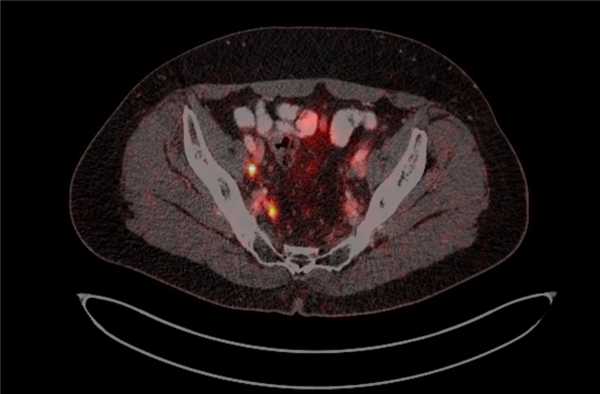

Рис. 4. ПЭТ-КТ изображения больного М. с поражением тазовых лимфоузлов

о Основная роль ПЭТ-КТ заключается в начальном установлении стадии и оценке биохимических рецидивов заболевания; не используется в диагностике или постановке Т-стадии

о ПЭТ-КТ с 11С-холином: ограниченная доступность, требует наличия циклотрона в клинике; возможность выявления опухоли в неувеличенных лимфоузлах и раннего вовлечения костного мозга; применяется при подозрении на рецидив заболевания